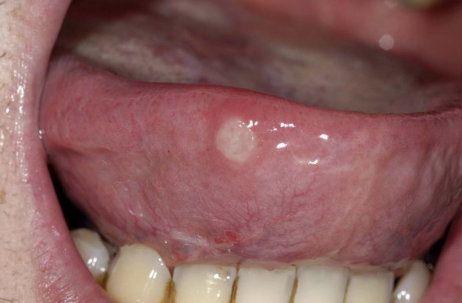

혓바늘은 누구나 일상에서 한 번쯤 경험하는 흔한 증상입니다. 작은 돌기처럼 올라와 따끔거리거나 음식 섭취 시 불편을 주며, 때로는 대화를 할 때도 신경이 쓰이곤 합니다. 많은 사람들이 혓바늘 없애는 방법을 검색하는 이유도 이런 생활 속 불편 때문입니다. 혓바늘 없애는법은 단순한 연고 사용에서부터 생활습관 관리, 병원 방문에 이르기까지 다양한 선택지가 있습니다. 이 글에서는 혓바늘 연고와 혓바늘 병원 관련 정보를 포함해, 혓바늘 없애는 방법을 폭넓게 정리해 보겠습니다.

혓바늘은 혀 표면에 국소적으로 나타나는 미세한 염증성 변화입니다. 일반적으로 피로, 수면 부족, 스트레스, 비타민 부족 등 다양한 요인과 연관이 있습니다. 저도 업무가 몰려 과로가 심했을 때 혓바늘이 자주 생겨 입안이 불편했던 경험이 있습니다. 이러한 개인적 경험에서 알 수 있듯이, 혓바늘 없애는 방법은 단순히 특정 치료에 의존하기보다 생활 전반을 점검하는 것이 기본입니다.

대부분의 혓바늘은 시간이 지나면서 자연스럽게 줄어들기도 합니다. 하지만 그 기간 동안 불편감이 크기 때문에 많은 사람들이 혓바늘 없애는법을 찾고, 연고나 병원 진료를 고민하게 됩니다.